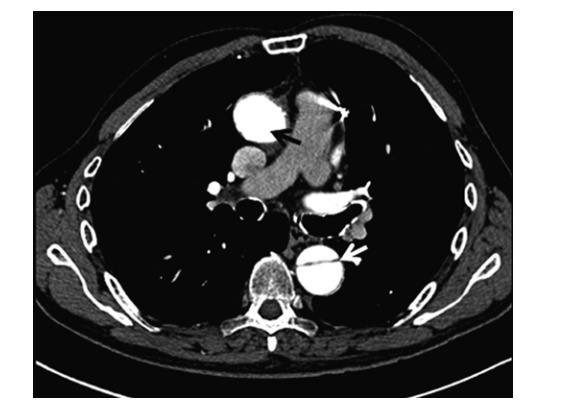

Aortic Dissection

Diagnosis